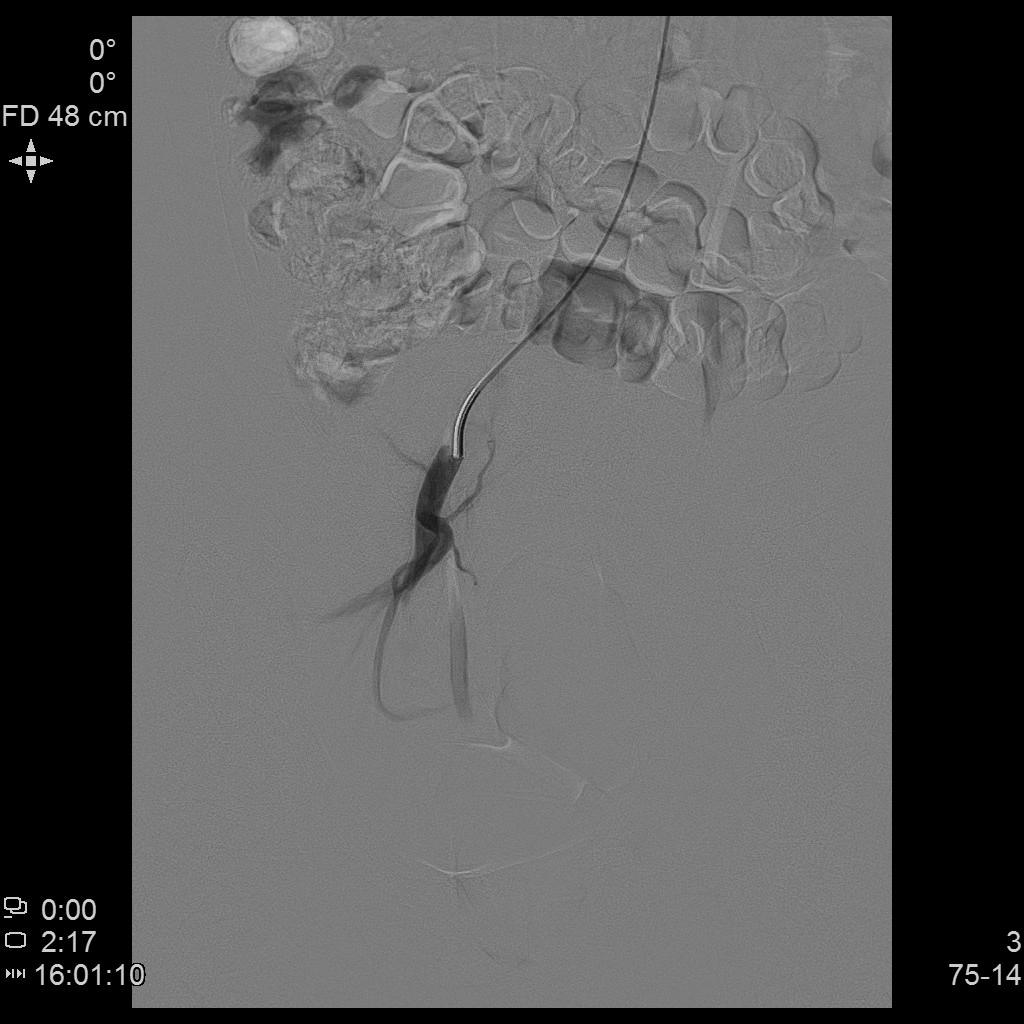

- 进一步超选插管右侧髂内动脉造影确认子动脉开口位置。

右侧髂内动脉造影

- 微导管进一步超选插管右侧子宫动脉主干造影确认位置。

右侧子宫动脉造影